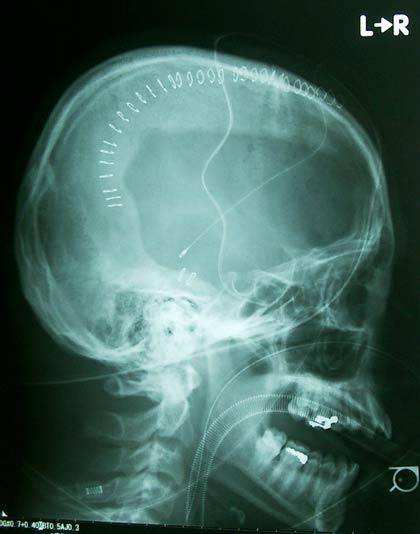

ภาพถ่ายเอกซเรย์ ตั้งแต่เมื่อ 3 ม.ค.2548 ที่ครอบครัวโคบายาชินำ มาแสดงหลังการผ่าตัดกะโหลกของยาซูฮิโกะ โคบายาชิ ลูกชาย ซึ่งได้รับบาดเจ็บที่สมองอย่างรุนแรง ต้องผ่าตัดส่วนหนึ่งของกะโหลกศีรษะออกไป  อาการบาดเจ็บเกิดขึ้นหลังเรียน ยูโดที่โรงเรียน ล่าสุดมี งานวิจัยแสดงว่าโดยเฉลี่ย มีเด็กเสียชีวิตปีละ 4 คน จากการเรียนยูโดในญี่ปุ่น เรื่องนี้ทำให้ผู้ปกครองตื่นตัวมากขึ้น เนื่องจากกำลังจะมีการนำวิชาศิลปะป้องกันตัว มาบรรจุเป็นวิชากีฬาบังคับในโรงเรียน.